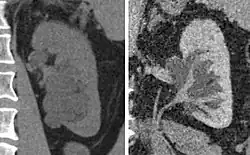

Peripelvic renal cysts may look like hydronephrosis on non-contrast CT (left image). However, CT urography (at right) reveals non-dilated calyces and pelvises.

Peripelvic renal cysts may look like hydronephrosis on non-contrast CT (left image). However, CT urography (at right) reveals non-dilated calyces and pelvises.